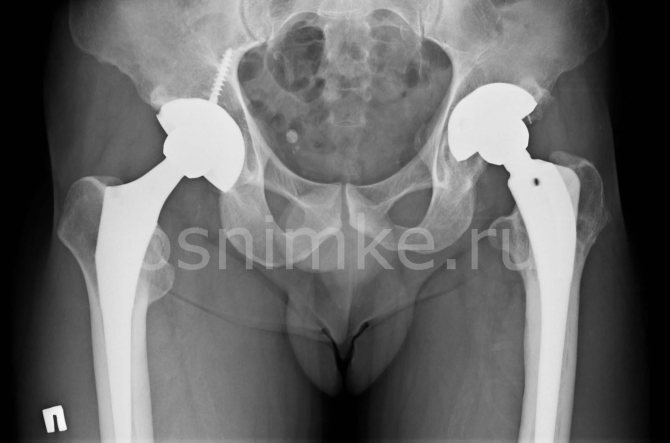

При посещении врача важно описать все тревожные симптомы и ситуации, которые могут стать показаниями к проведению рентгена: травмы, боли и отечности в области таза, звуки при движениях (хруст и щелчки), переломы, послеоперационная оценка протезов, нарушение развития, хромота при ходьбе. Также рентген делают грудничкам с подозрениями на дисплазию тазобедренного сустава (вывих, подвывих, предвывих).

Смещение протеза

В результате данного явления вживленный имплантат не только теряет фиксацию и расшатывается, но и приводит к постепенному или резкому изменению длины ног. В таком случае требуется немедленная консультация у врача и повторная операция на конечности. К основным причинам можно отнести следующие:

- неправильная установка имплантата;

- недостаточный контакт между поверхностями сустава и протеза;

- сильные нагрузки на имплантат;

- непрочное соединение компонентов изделия.

К особым случаям относится расшатывание и повреждение отдельных компонентов протеза. В достаточно короткий срок может разрушится структура полиэтиленового вкладыша или бедренной ножки. Вывих или перелом эндопротеза также случается достаточно часто. Поэтому в обязательном порядке следует соблюдать рекомендации специалистов, а также осуществлять диагностические и профилактические мероприятия. Это гарантировано поможет предотвратить появление негативных последствий операции.